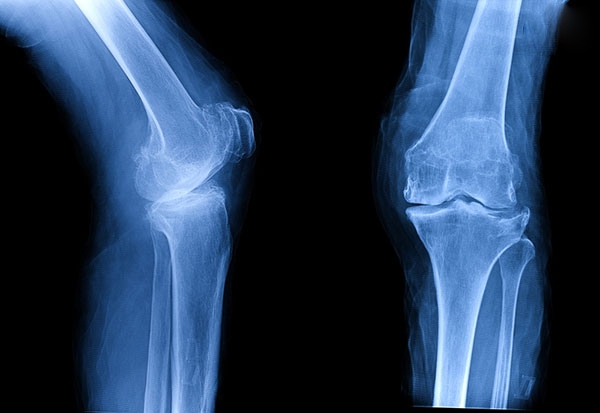

• Chụp phim

Hình ảnh thu được từ việc chụp X – quang, cộng hưởng từ MRI hay CT scan cho phép bác sĩ định mức được độ hao mòn của sụn khớp, dây chằng, gân và cơ.

Tổn thương do viêm khớp gối

Mức độ tổn thương sụn khớp và xương dưới sụn sẽ hiện rõ trên hình ảnh X – quang

Sau khi tổng hợp các dữ liệu, bác sĩ sẽ hội chẩn và đưa ra kết luận chính xác về loại viêm khớp, nguyên nhân và tình trạng thực tế của khớp gối. Từ đây, một phác đồ điều trị chi tiết nhanh chóng được đưa ra để bắt đầu công cuộc hàn gắn vết thương và phòng ngừa biến chứng.